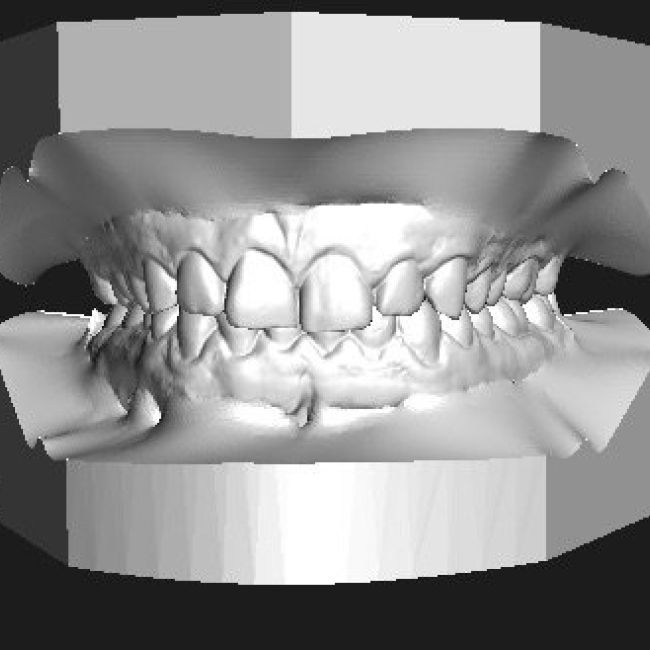

En los centros de Imagen Diagnóstica Dental Dr. Mayor ofrecemos una amplia variedad de servicios, gracias a la moderna aparatología con las que contanmos. Las pruebas diagnósticas que realizamos en nuestro centro son las siguientes: